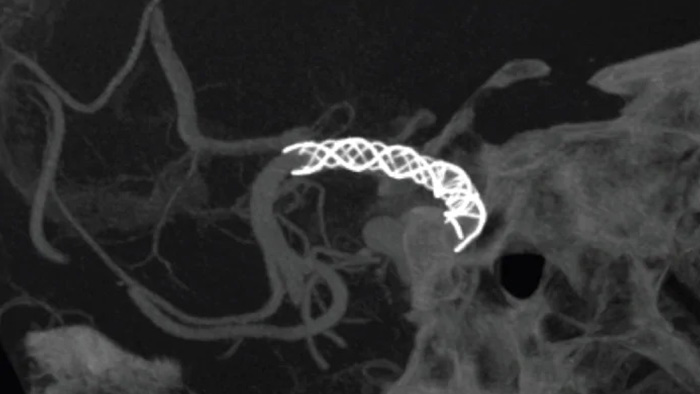

Улучшите визуализацию эндоваскулярных стентов, различных устройств, в том числе для отведения потока, а также морфологии сосудов вплоть до перфорантных вен с помощью SmartCT Vaso. Этот метод сбора данных основан на получении КТ-изображений с помощью конического пучка и внутриартериальной инъекции контраста. Его все чаще применяют для последующего исследования пациентов, перенесших операцию по лечению аневризмы с применением стентов, отклоняющих поток, чтобы проверить расположение устройства.